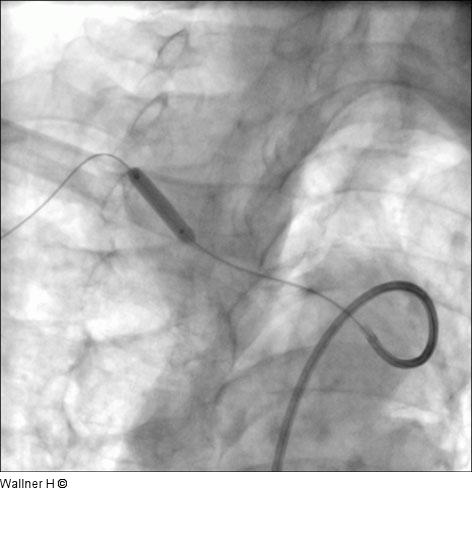

Abbildung 3: Vordilatation

Vordilatation mit Ballon.